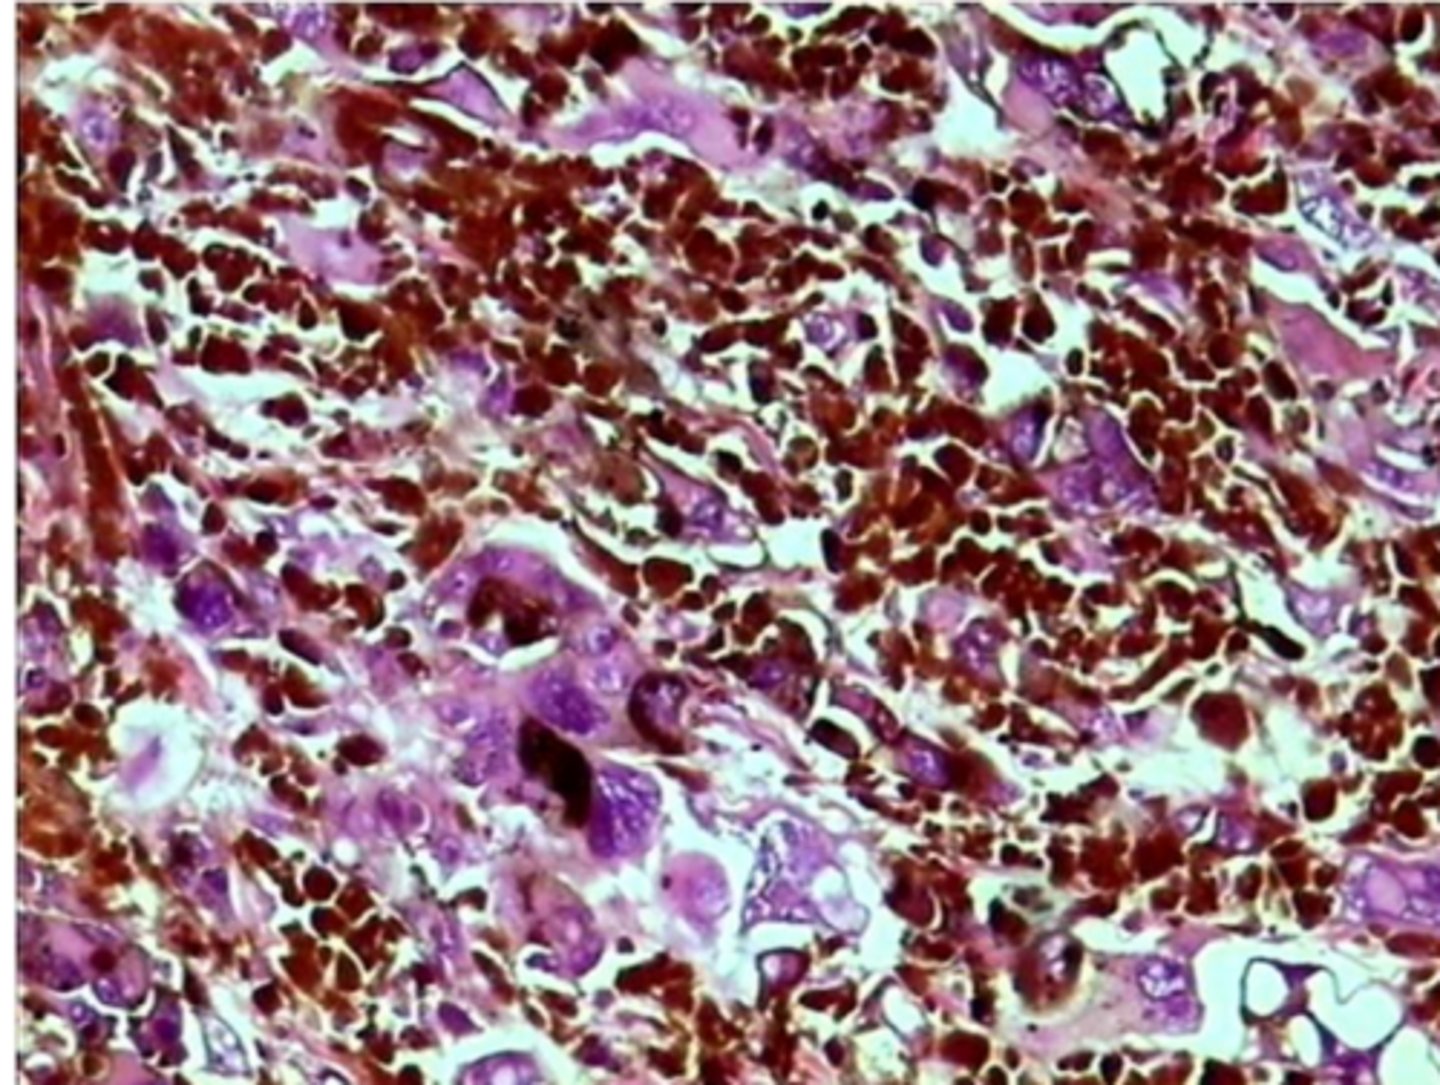

Melanoma: izteikta šūnu atipija un melanīna sintēze

6

New cards